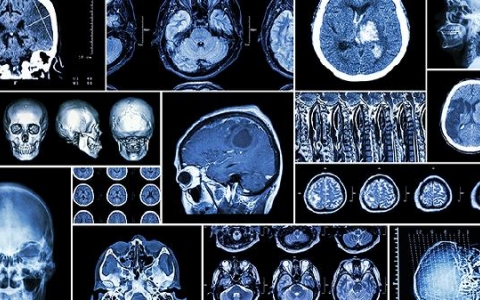

如何治疗脑震荡?脑震荡是指头部受到外力打击后的短暂脑功能障碍。脑震荡后,部分患者会出现头痛等后遗症,但不会对神经系统造成损害。主要症状有意识障碍,程度轻,时间短

脑瘤会引起走路不稳吗?随着脑肿瘤体积的不断增大,会对周围正常脑组织形成压迫以及水肿,造成颅内压逐渐升高,患者逐步出现头痛头晕呕吐,肢体乏力,偏瘫,嗜睡昏迷等症状

1、综合治疗①综合治疗及个体化治疗,在疾病发展的不同时间,针对不同病情、病因采取有针对性的综合治疗和个体化治疗措施。②积极改善和恢复缺血区的血液供应,促进脑微循

蛛网膜囊肿形成的原因是什么?蛛网膜囊肿是一种先天性疾病,其病因相对简单,是由发育期蛛网膜分裂异常引起的。由于这是一种良性病变,大多数时候表现不明显,所以不需要做

脑溢血是一种常见的病症,不仅多发而且病症非常严重,一般脑溢血病人会有头晕头痛、突然口眼歪斜、流鼻血以及身体一侧发麻的前兆,所以在发现家里老人有这些症状时必须引起

大面积脑梗死后如何治疗?在各种疾病中,脑梗死是一种非常严重的疾病,因为它可能导致偏瘫,在严重的情况下无法照顾自己。特别是对于一些大面积脑梗死患者来说,情况更危险

颅内肿瘤无论是良性肿瘤还是恶性肿瘤肿瘤会压迫周围脑组织造成脑水肿引起脑细胞坏死造成神经功能障碍常有癫痫发作所以脑瘤术后病人尽量不要喝酒防止癫痫发作但脑瘤患者术后

突发性脑溢血也被称为脑出血,一般好发于老年人群较多,而突发性脑出血是由于脑部的血管突然出现破裂,同时脑部的血液会出现压迫脑细胞的情况,容易导致脑部淤血或者是脑部